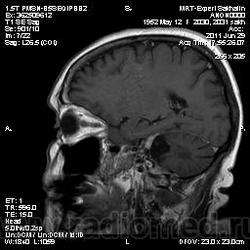

Абсолютно с Вами согласна Helios - это рецидив. Рискну предположить что убирали либо невриному левого тройничного нерва, либо менингиому верхушки пирамиды височной кости.

Со слов сына женщины-удаляли невриному.

согласен за такой рецидив. Если бы удаляли зло- задумался бы.

Нет левого клочка мозжечка что объясняет и головокружение и головные боли ... вместе с узелком образуют клочково-узелковую дольку мозжечка, филогенетически это наиболее древняя часть мозжечка, так что повреждение клочка вызывает очень выраженные и стойкие вестибулярные нарушения ...

Нет левого клочка мозжечка что объясняет и головокружение и головные боли ... вместе с узелком образуют клочково-узелковую дольку мозжечка, филогенетически это наиболее древняя часть мозжечка, так что повреждение клочка вызывает очень выраженные и стойкие вестибулярные нарушения ...